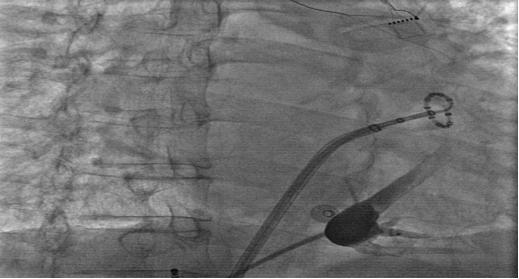

经过充分的术前准备,南大二附院心内科心律失常团队通力合作,先后为两位持续性房颤患者成功实施了该项手术,Marshall静脉细小,解剖位置变异较大,容易漏掉,因此需首先定位该静脉。通过冠状静脉造影寻找Marshall静脉,之后送入导丝及球囊。两例房颤患者术中Marshall静脉化学消融后,对于导管消融难以实现透壁损伤的左肺静脉和左心耳交界嵴部区域电位消失,左肺静脉隔离很快完成,同时仅仅消融几个点就彻底阻断了二尖瓣峡部,患者最终成功恢复了窦性心律。

冠状静脉造影后,找到Marshall静脉